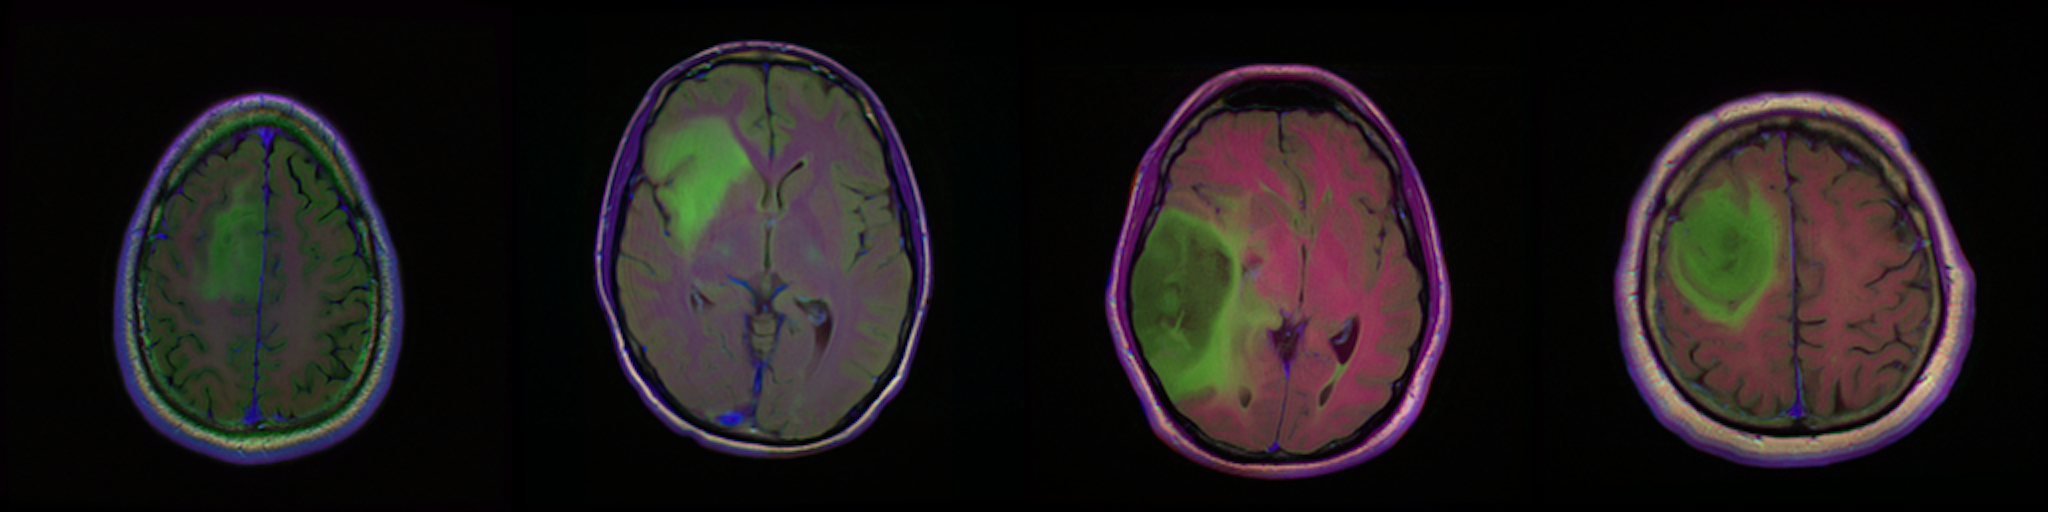

![]() |

|---|---|---|

| DSC 94% | DSC 91% | DSC 89% |

来自三家不同机构的验证病例的定性结果,DSC 分别为 94%、91% 和 89%。绿色轮廓表示真实标签,红色则为模型预测结果。图像显示的是预处理后的 FLAIR 模态。